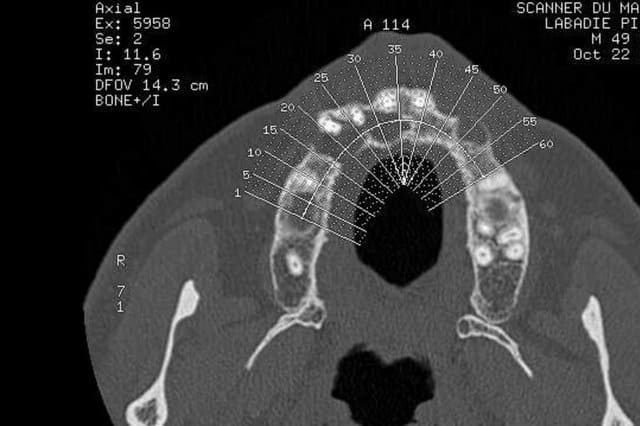

Voilà j'ai mieux que la gutta (pas de fistule visible en ce moment de toute façon )

Un scan. Voici quelques extraits.

Donc on extrait tout ce qui reste devant, on est d'accord ?

il semble y avoir une communication avec les sinus frontaux visible sur les coupes ,personnellement je serai très méfiant sur les extractions,que je déléguerais car les suites risques de ne pas être si simples, et ne les ferais pas sans avoir préalablement défini un plan de traitement post chirurgical surtout si le patient ne se plaint de rien actuellement;car ce type de situation mal anticipée peut amener des conflits.